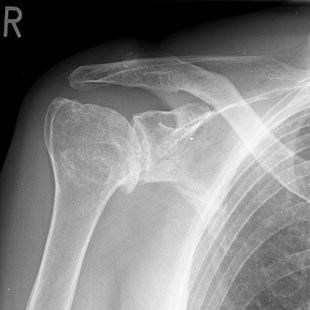

Schultergelenkarthrose oder Omarthrose

(Verschleiß im Schultergelenk)

Unter einer Omarthrose versteht man den Gelenkverschleiß im Schultergelenk im Sinne eines Defektes der Knorpelstrukturen der gelenkbildenden Anteile von Humeruskopf und Schultergelenkspfanne.